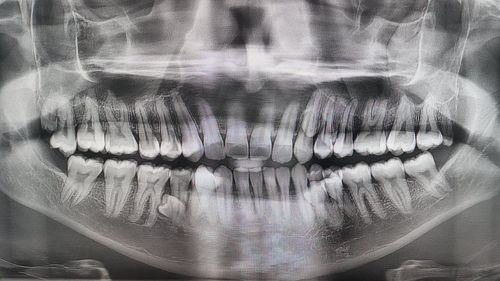

Gia đình anh quyết định kiểm tra và đếm chúng. Sau đó, người ta phát hiện ra anh có 38 chiếc răng. Sau đó, chụp X-quang răng cho thấy anh có thêm bốn chiếc răng nữa trong hàm chưa mọc. Đến đầu năm 2023, rõ ràng là anh có 42 chiếc răng.